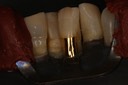

Wayne Chin #15 prep